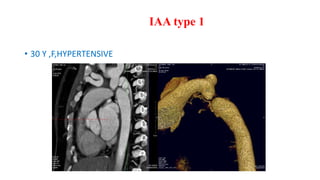

I AA

According to the Celoria-Patton classification of IAA ;

type A is defined as interruption distal to the left subclavian artery (42%

of cases);

type B, the interruption is between the left common carotid artery and

subclavian artery (53%).

type C, the interrupted segment is between the innominate artery and

left common carotid artery (4%).

• Occluded Aortic segment

• Mostly at the arch

• Associated with VSD, PDA, DORV

• Radiographic features:

• No aortic knob, large PA

• Neonatal pulmonary edema

Interrupted Aortic Arch

IAA type 1

• 30 Y ,F,HYPERTENSIVE